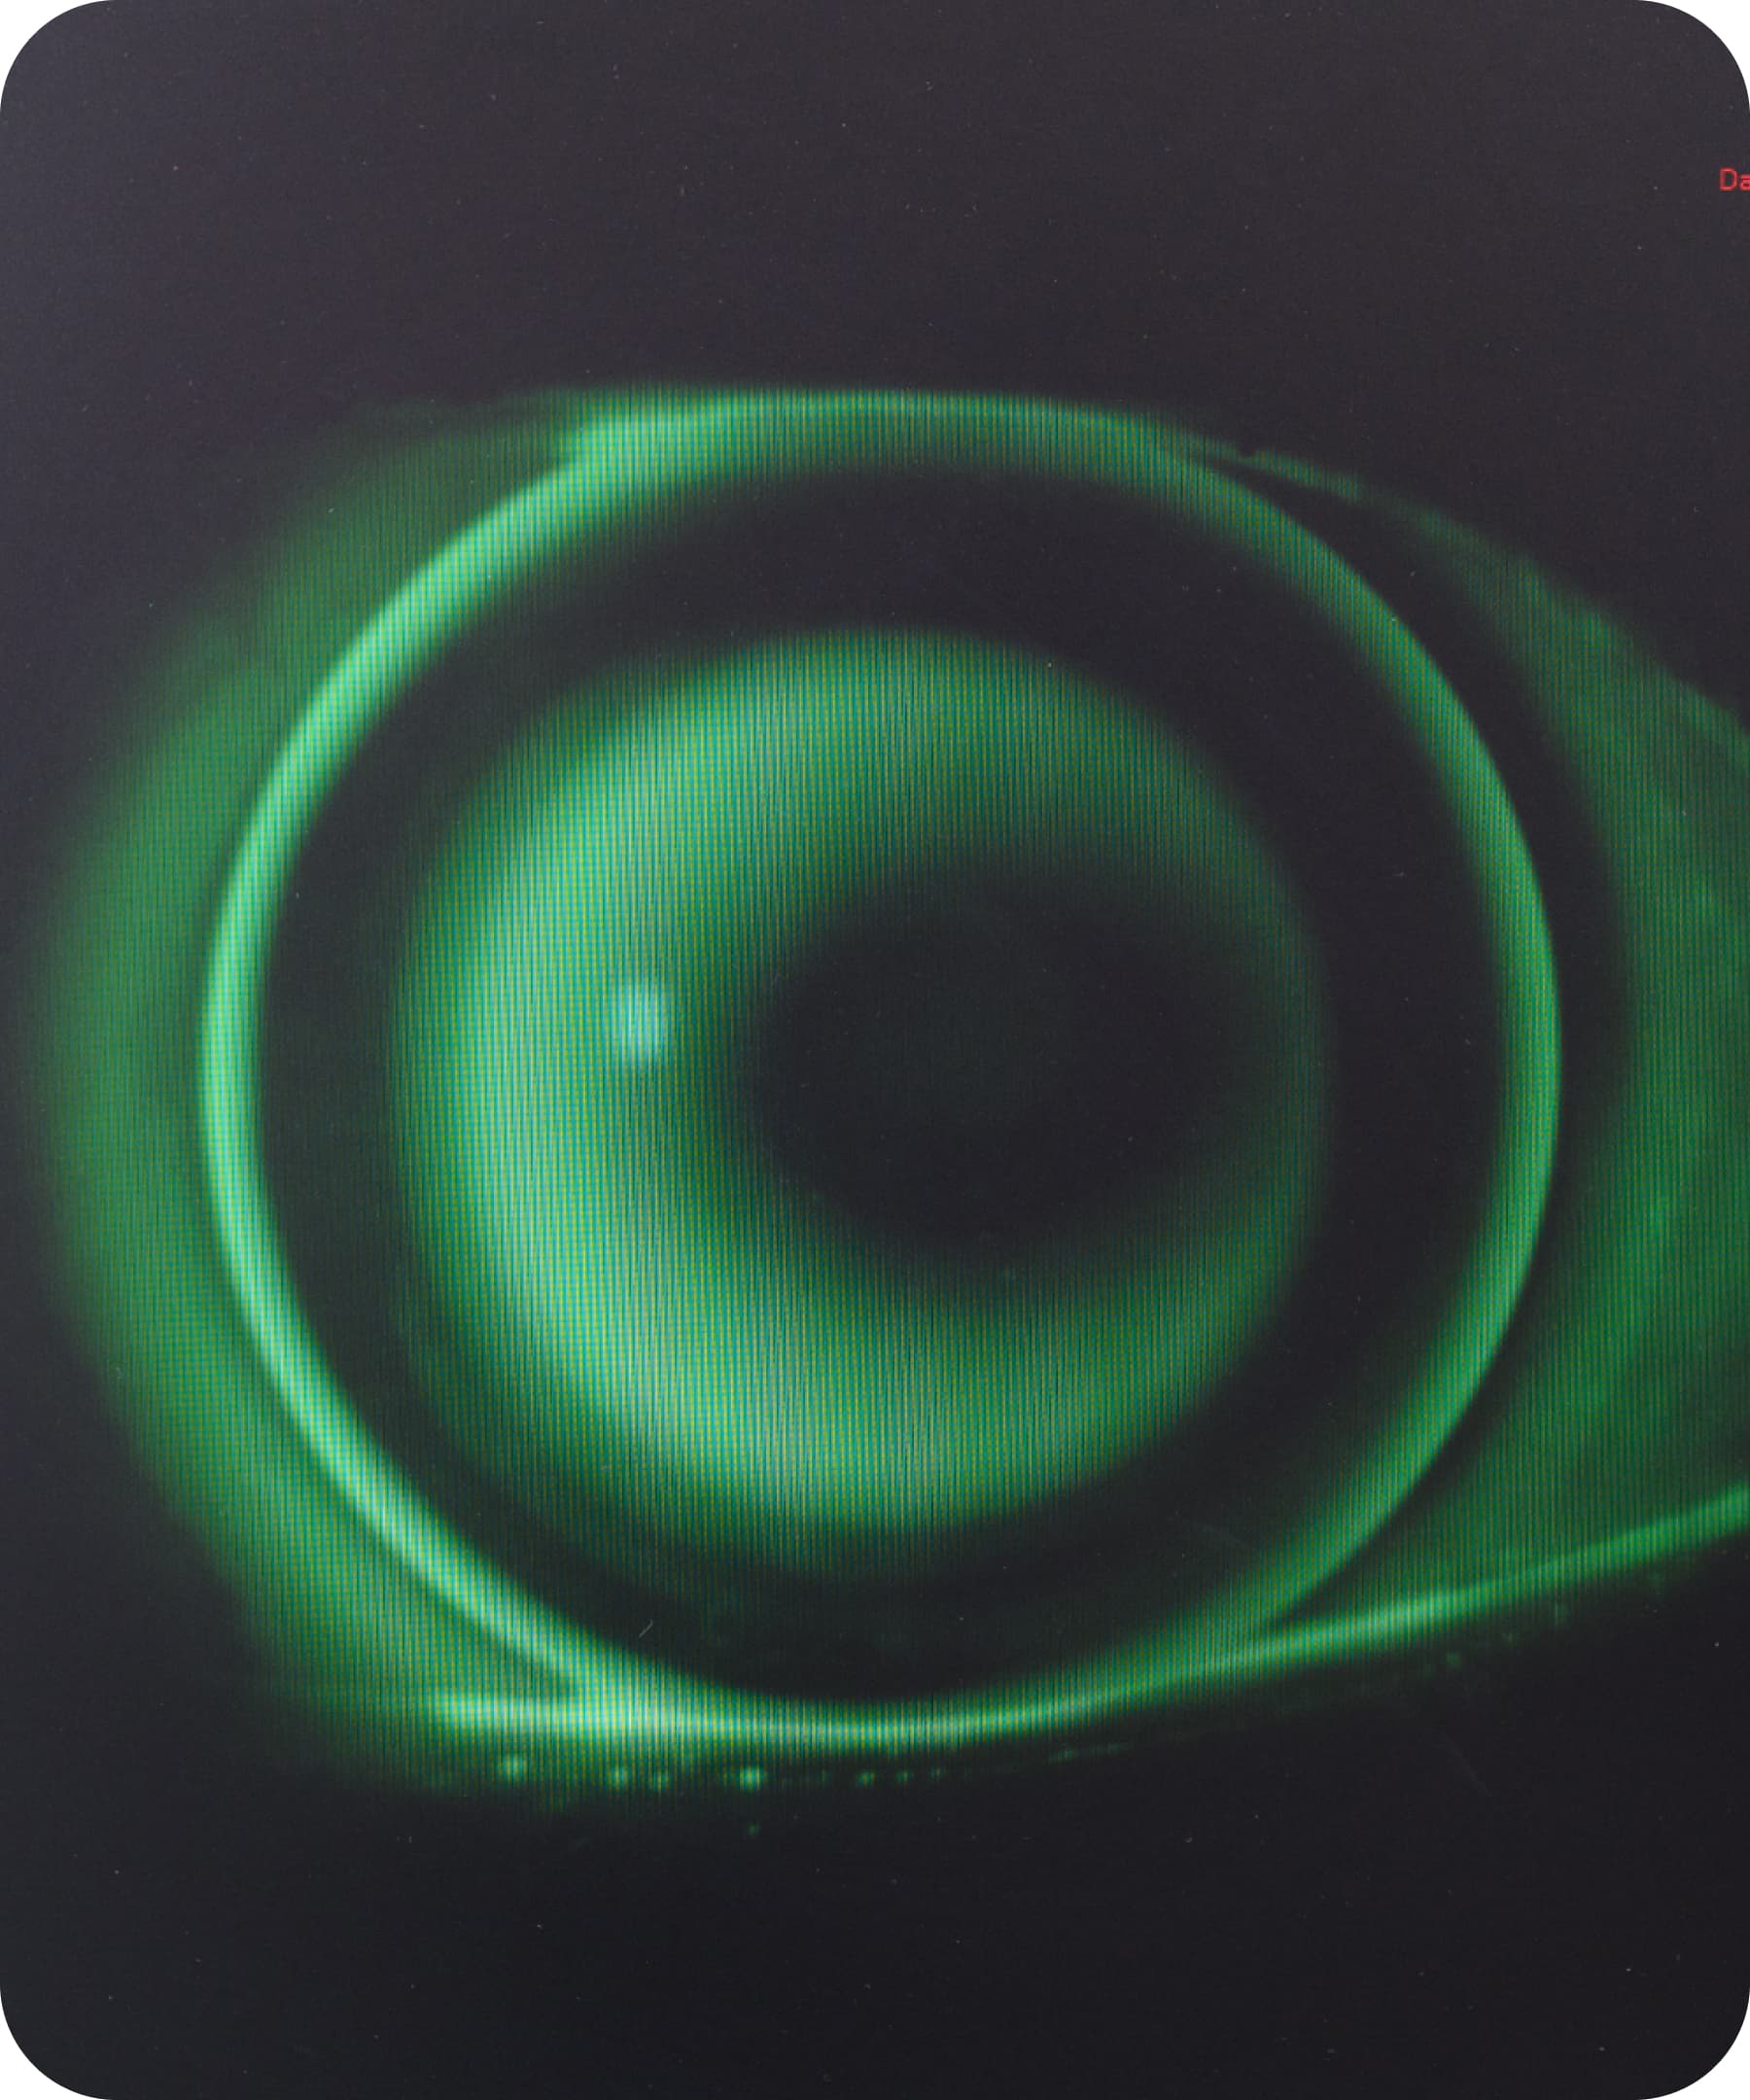

L'ortocheratologia è una tecnica innovativa e non invasiva che corregge i difetti visivi con speciali lenti notturne. Indossate durante il sonno e rimosse al risveglio, rimodellano temporaneamente la curvatura corneale, permettendovi di vedere bene tutto il giorno senza occhiali o lenti a contatto tradizionali.

Grazie alla geometria inversa e all'elevata permeabilità all'ossigeno, queste lenti semirigide gas permeabili garantiscono un trattamento sicuro, confortevole ed efficace. Il rimodellamento è reversibile, quindi per mantenere i benefici è necessaria una costante applicazione.

Le lenti ortocheratologiche modellano delicatamente la superficie corneale durante il sonno, riducendone lo spessore in modo controllato e correggendo temporaneamente il difetto visivo.

Per capire la precisione del trattamento, basti pensare che una riduzione di due diottrie equivale a un assottigliamento di soli 12 micron, mentre un capello umano ha uno spessore medio di 125 micron.